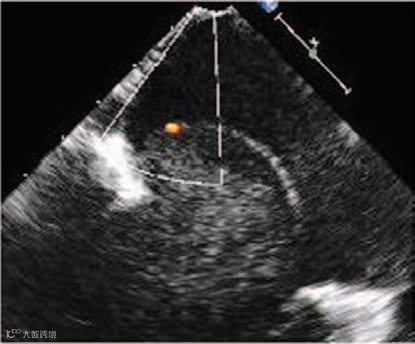

发现一个5.4×3.9厘米的低回声肿瘤,该肿瘤脱垂穿过二尖瓣,导致左心室流入道梗阻(图2;视频I)。肿瘤质地柔软、表面光滑,有蒂起源于房间隔。

显示肿瘤内部有动态烟雾样回声(提示存在自发显影,图3;视频I)。M型超声显示肿瘤在收缩期两次回弹至左心房腔,产生M形信号(图4;视频II),提示肿瘤内部充满液体而非凝血,呈现血球样外观。彩色多普勒显示有血流流入(图5)和流出肿瘤(图6),且主要发生在舒张期(图7和8;视频III),提示血供来源于冠状动脉。

图5